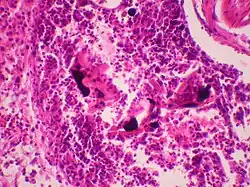

Rtęcica, zatrucie rtęcią – choroba wywołana poprzez akumulację rtęci w organizmie człowieka. Dochodzi do niej głównie w wyniku spożywania zanieczyszczonego pokarmu, używania urządzeń zawierających rtęć (jak np. termometry), narażenia zawodowego (wydobycie złota) oraz podczas zabiegów dentystycznych z wykorzystaniem amalgamatów[1]. Rtęć uszkadza centralny układ nerwowy człowieka oraz układ hormonalny. Może doprowadzić do uszkodzenia warg, zębów oraz dziąseł. Długi czas styczności ze związkami rtęci prowadzić może do urazów mózgu oraz śmierci. Wpływa negatywnie na rozwój płodu oraz niemowlęcia. Szczególnie niebezpiecznymi związkami rtęci są metylortęć i dimetylortęć, które były stosowane jako pestycydy i środki przeciwgrzybiczne.